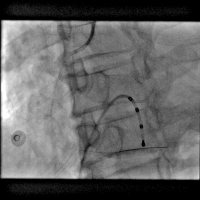

第二次手术过程

手术时间: 2016年11月。

术中用药: 术中肝素6000单位。

造影结果: 左前降支近段闭塞,回旋支中远段90%狭窄。

手术过程(一): 将Fielder XT 导丝送入回旋支远端真腔,沿回旋支导丝送入Trek 2.5×20 mm球囊到回旋支中段8 atm×10 s预扩,沿导丝Firebird 2.5×29 mm药物支架一枚到回旋支中远段8 atm×12 s释放。

手术过程(三): 微导管支持下ASAHI Gaia 1st 导丝通过前降支真腔。

手术过程(五): 沿导丝送入Firebird 2.5×33 mm药物支架一枚至前降支中段10 atm×12 s释放,沿导丝送入Firebird 3.0×23 mm药物支架一枚至前降支近段14 atm×12s释放。